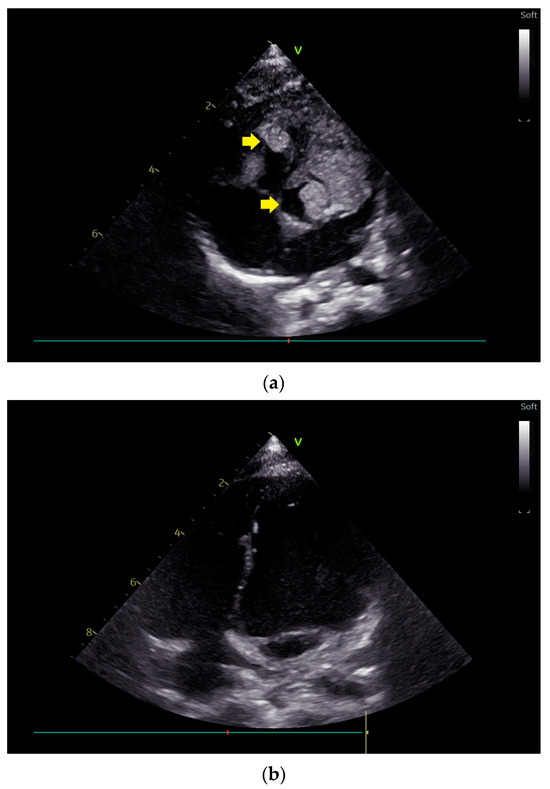

Figure 1 presents echocardiographic images of multiple rhabdomyoma in a neonate diagnosed with TS, in the left and right ventricle (a) with a spontaneous partial regression in the first two years of life (b).

Figure 1.

Transthoracic echocardiography showing multiple ventricular rhabdomyomas in the left and right ventricle (yellow arrows) in a neonate diagnosed with tuberous sclerosis (a) and their spontaneous partial regression at the age of 2 years (b).